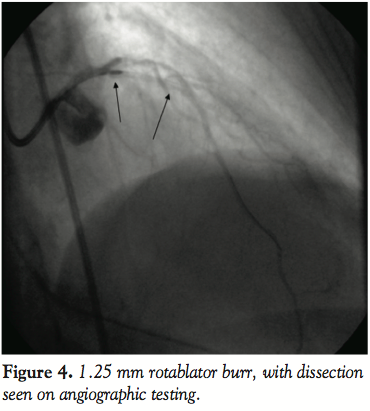

Given the limited revascularization options, we decided to proceed with careful rotational atherectomy. A Rotablator Floppy wire was tried again and did cross the lesion at this point. Gentle and extremely careful “pecking” with < 15 second runs and avoiding of > 5,000 rpm decelerations at 150,000 rpm was performed with frequent monitoring of contrast for perforation and dissection propagation (Figure 4). Four passes were performed without worsening dissection or perforation. Subsequently, noncompliant 2.25 mm balloon inflations did appear to yield the lesion and a 2.25 x 23 mm drug-eluting stent was implanted with excellent angiographic results and infarct resolution (Figure 5). Further postdilation was performed with a 2.75 mm noncompliant balloon to ensure excellent stent expansion (Figure 6). The patient was brought back for staged PCI to the right coronary artery, which demonstrated complete patency. There was no angiographic restenosis of the LAD stent at 3 months.

Rotational atherectomy in the presence of dissection is contraindicated. Concerns include perforation and more commonly propagation of spiral dissection through potential entrapment of dissection flap in the rotational motion of the burr.

On this occasion we describe the use of RA in the combined setting of acute thrombotic STEMI with an undilatable lesion and post-ballooning type C dissection. Although early rotational atherectomy was contemplated and attempted, the rotawire would not traverse the lesion. Finally, careful RA was performed in the presence of a type C dissection with subsequent stenting. Techniques to avoid complications in this perilous setting may include small burr size (1.25 mm in this case), gentle “pecking” advancement and frequent angiographic monitoring between ablations to ensure absence of complications. The small caliber burr (1.25 mm) is likely quite important in this type of a situation and may prevent further complications such as dissection propagation or perforation in an already tenuous scenario. Most often dissections in calcified lesions may flank the most stenotic/calcific site and not actually be located at the calcified segment; in such a case, it may be advised to perform very localized rotablation and avoid multiple long “smoothing runs” to “polish” the lesion segment in order to avoid dissection flap entrapment and subsequent dissection propagation or perforation. Although operators may be somewhat reticent to initiate GPIIb/IIIa inhibition until late in rotablation to avoid catastrophic bleeding from perforations or in case of surgery requirement for dissection. In this case, further thrombus burden may have been prevented from early initiation of GPIIb/IIIa inhibitor.